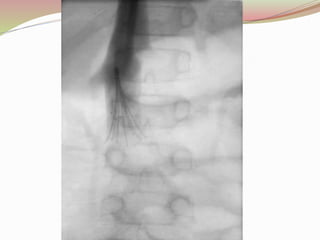

Venography -Popliteal Vein Thrombosis

Venography

 It detects thrombi in both calf and thigh

 It can conclude and exclude the diagnosis of DVT

when other objective testings are not conclusive.

 Advantages

 It is useful if the patient has a high clinical probability

of thrombosis and a negative ultrasound.

 It is also valuable in symptomatic patients with a

history of prior thrombosis in whom the ultrasound is

non-diagnostic.

Disadvantage

 It can primary cause of DVT in 3% of patients who

undergo this diagnostic procedure.

 An invasive and expensive.

 Although Venography was once considered the gold

standard for diagnosis of DVT, today it is more

commonly used in research environments and less

frequently utilized in clinical practice.